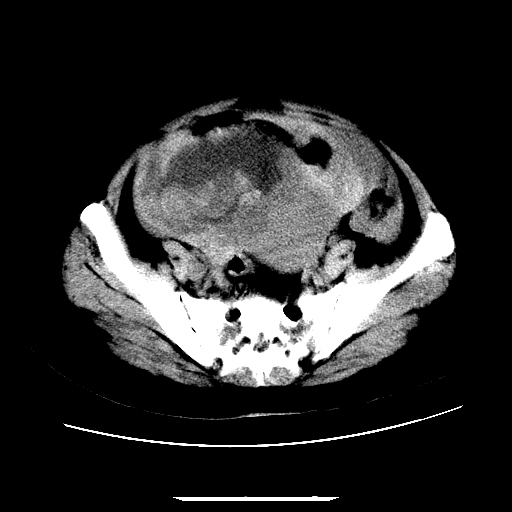

f,45y.怀孕4月晕倒,b超提示死胎,有手术结果,请展开讨论后明天告诉。

膈下-肠间隙内见气体密度影,子宫轮廓显示不清,宫腔-腹腔积液,首选考虑---子宫破裂出血。

1)宫腔妊娠。2)子宫破裂出血,腹腔及盆腔积血。

怀孕4个月晕倒,病史就这么简单?有没有腹痛呢?腹腔内有没有气体?窗宽太窄了脂肪组织与气体已不好分。如果有气体,那就是空腔脏器穿孔,如胃肠穿孔。如没有气体,就考虑子宫破裂或宫外孕破裂。正常怀孕子宫破裂很少见,有可能是宫外孕。极有可能是残角子宫怀孕破裂。腹腔怀孕破裂也有可能。

感谢同行们的高见。手术结果:子宫破裂出血。

我们的诊断是:腹、盆腔积液(考虑腹盆腔脏器破裂出血);宫腔妊娠。让人纳闷的是当时我们没有经验,现在回头看看分析:4月宫腔妊娠:1、洋膜囊不可能紧贴胎体这么小;2仔细看看子宫后壁肌层模糊不清;3腹、盆腔液体来源原因?4、45岁高龄妊娠有晕倒。由此可大胆诊断:宫腔妊娠子宫破裂出血。